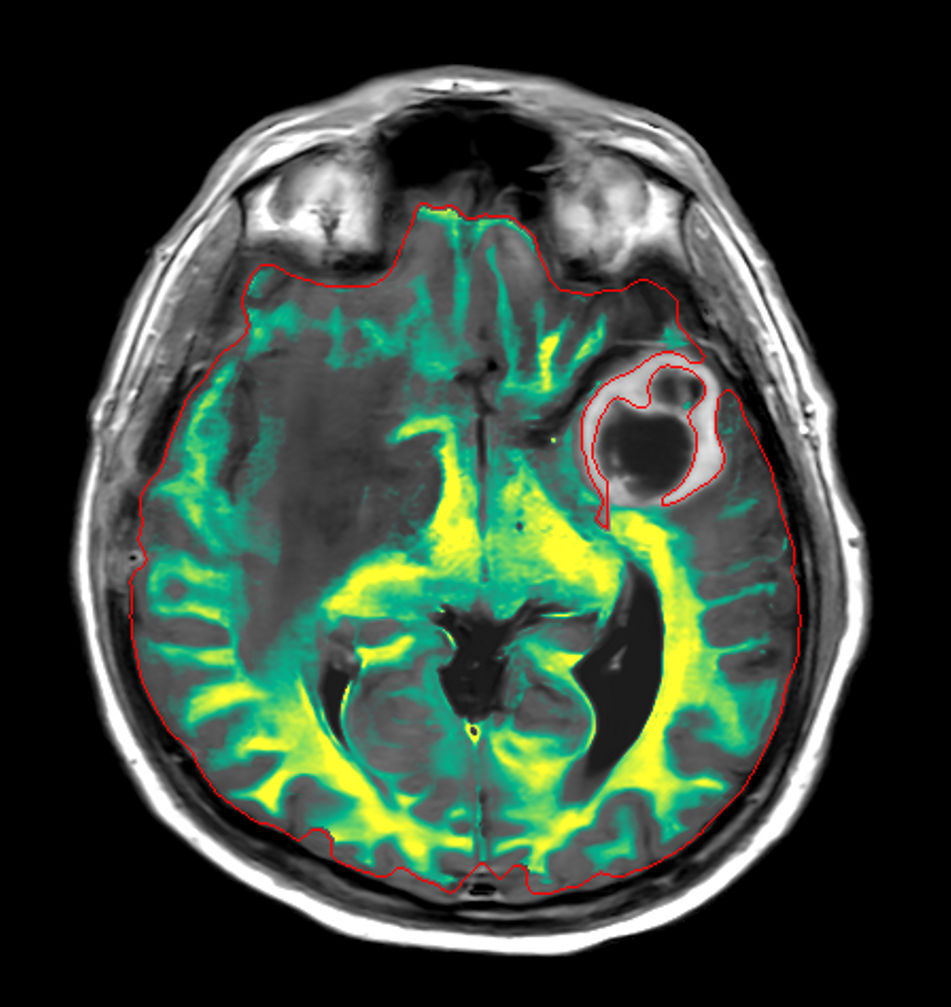

Patient information

Patient with a large brain lesion. AI based SmartSpeed is utlized to shorten scan time without compromise in image quality. Advanced imaging techniques like pCASL and 3D APT are used to perform contrast-free brain imaging to assess perfusion and tumoral activity. SWIp 3D susceptibility weighted offers the high sensitivity required to visualize deoxygenated (venous) blood or calcium deposits. A single synthetic (SyntAc) brain quantification scan is added. The resulting data of this scan can be used as input for advanced third party processing software* to synthesize MR images with different contrasts, brain parenchyma fraction maps and/or brain segmentation maps.

3D T1w TFE (Axial reformat)Post-Gado

-